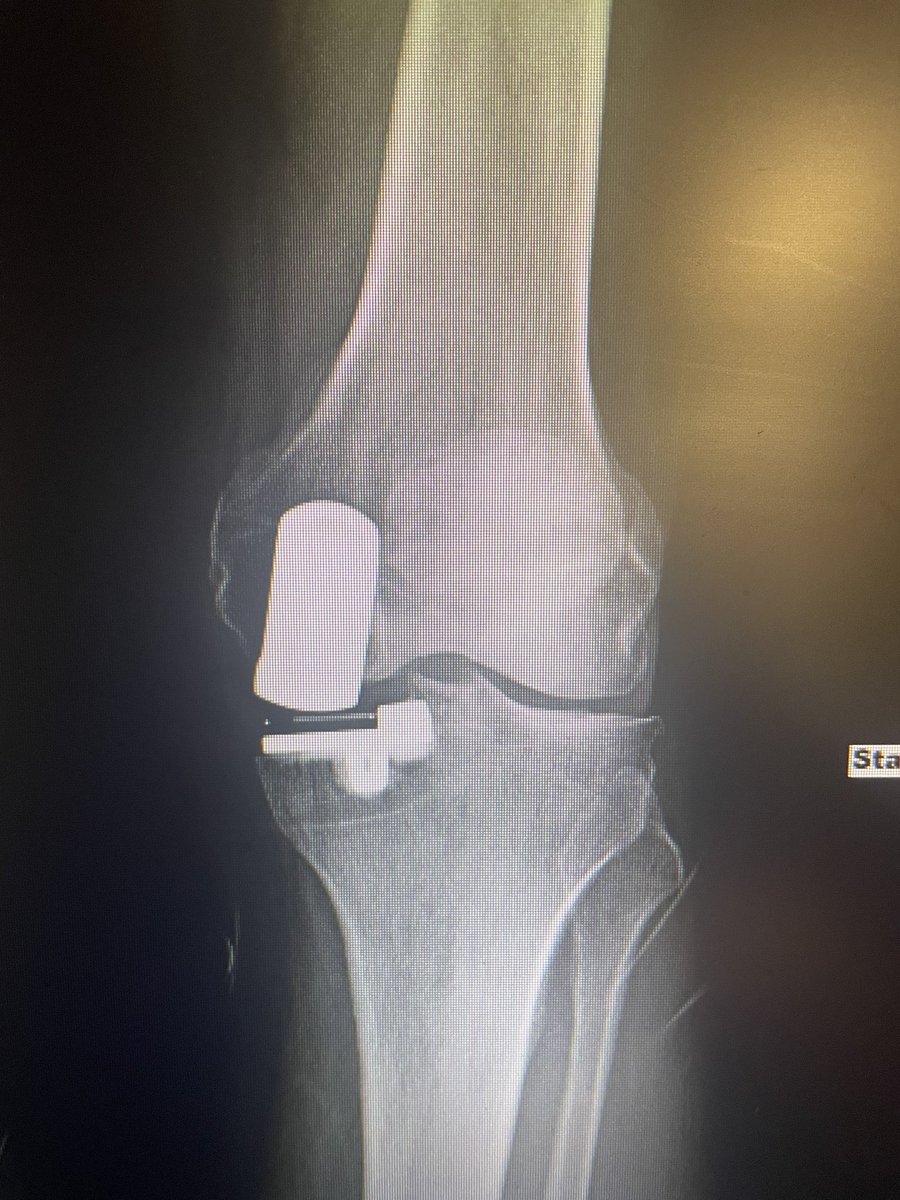

#orthotwitter Joint commission guidelines now state that OR temp must be between 68-73 For a total joints room this is very warm - cement gets too doughy too fast - what is everyone doing if held to this guideline? We are mixing for less time - using medium visc cement

Implant ID? Is this the Zimmer one that has NOT been recalled? Currently asymptomatic